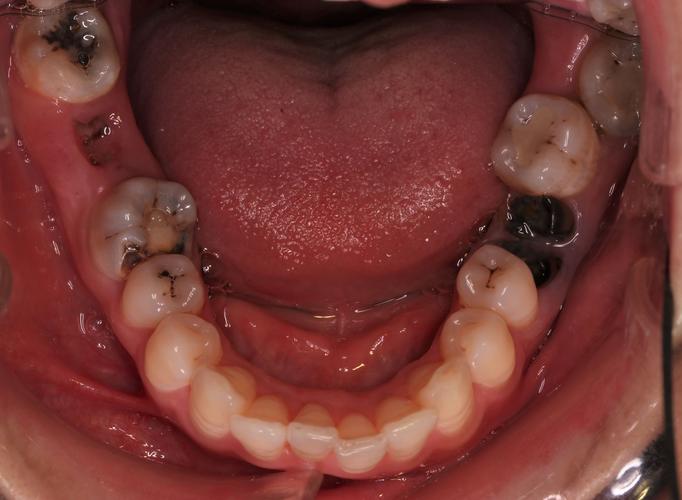

牙齿矫正的核心原理是通过施加持续、温和的力,引导牙齿在牙槽骨中移动,最终排列整齐、咬合协调,目前广州主流的矫正方式可分为以下几类,每种方式在美观度、舒适度、价格及适用人群上各有侧重:

首次就诊需进行全面检查,包括口腔内视镜检查、牙齿模型拍摄、头颅侧位片、全景片等,医生会分析牙齿排列、咬合关系、骨骼情况及面部美学,制定初步方案,患者需主动沟通自身需求(如美观、时间预算),确认方案后即可预约戴牙套。